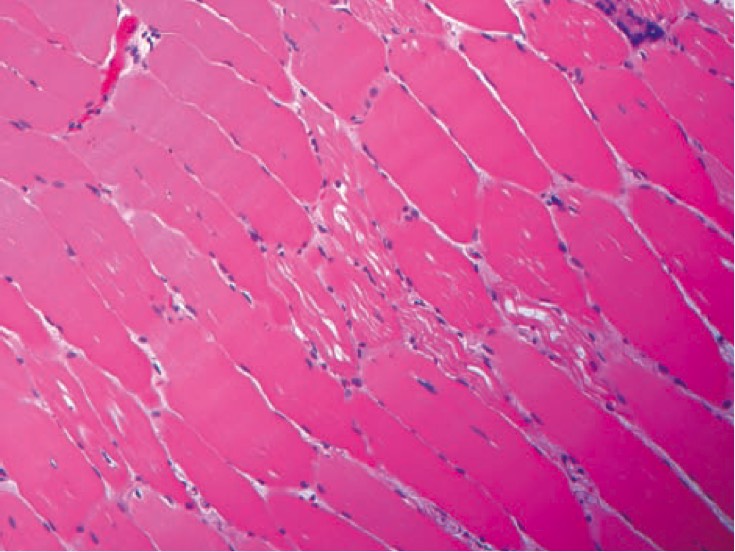

1059. У 66-летнего мужчины выраженная мышечная слабость и трудности при отлучении от аппарата ивл. биоптат поперечно-полосатой мышцы приведен на микрофотографии клеточные вакуоли положительно окрашиваются кислой фосфатазой, наиболее вероятен дефицит